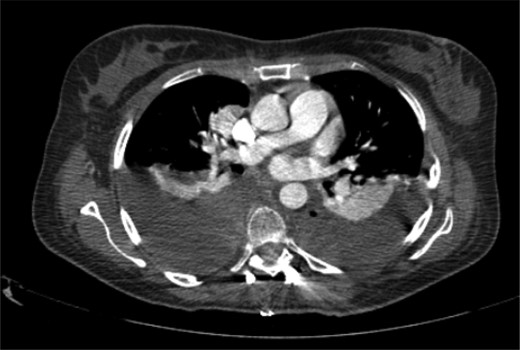

The patient started the pulmonary rehabilitation protocol by the second postoperative day, showing encouraging progression. However, by the third day, she initiated complaints of progressive dyspnea with associated impaired gas exchange. A CT scan confirmed bilateral hemothorax requiring bilateral thoracentesis (Fig. 4), after which she immediately recovered from the previous symptoms.

It was only by the 19th postoperative day, which the patient showed worsening of her general status with fever, dyspnea, decreased gas exchange and an increase in inflammatory markers. A new CT scan was performed, revealing a moderate fluid collection in both lungs, compatible with empyema (Fig. 5). The patient evolved to a septic state, which required her to be transferred to the intensive care unit.

Postoperative thoracic CT scan; large septated empyema, extending from the surgical site to both pleural cavities, was found to be the cause of deterioration of the patient's general condition.